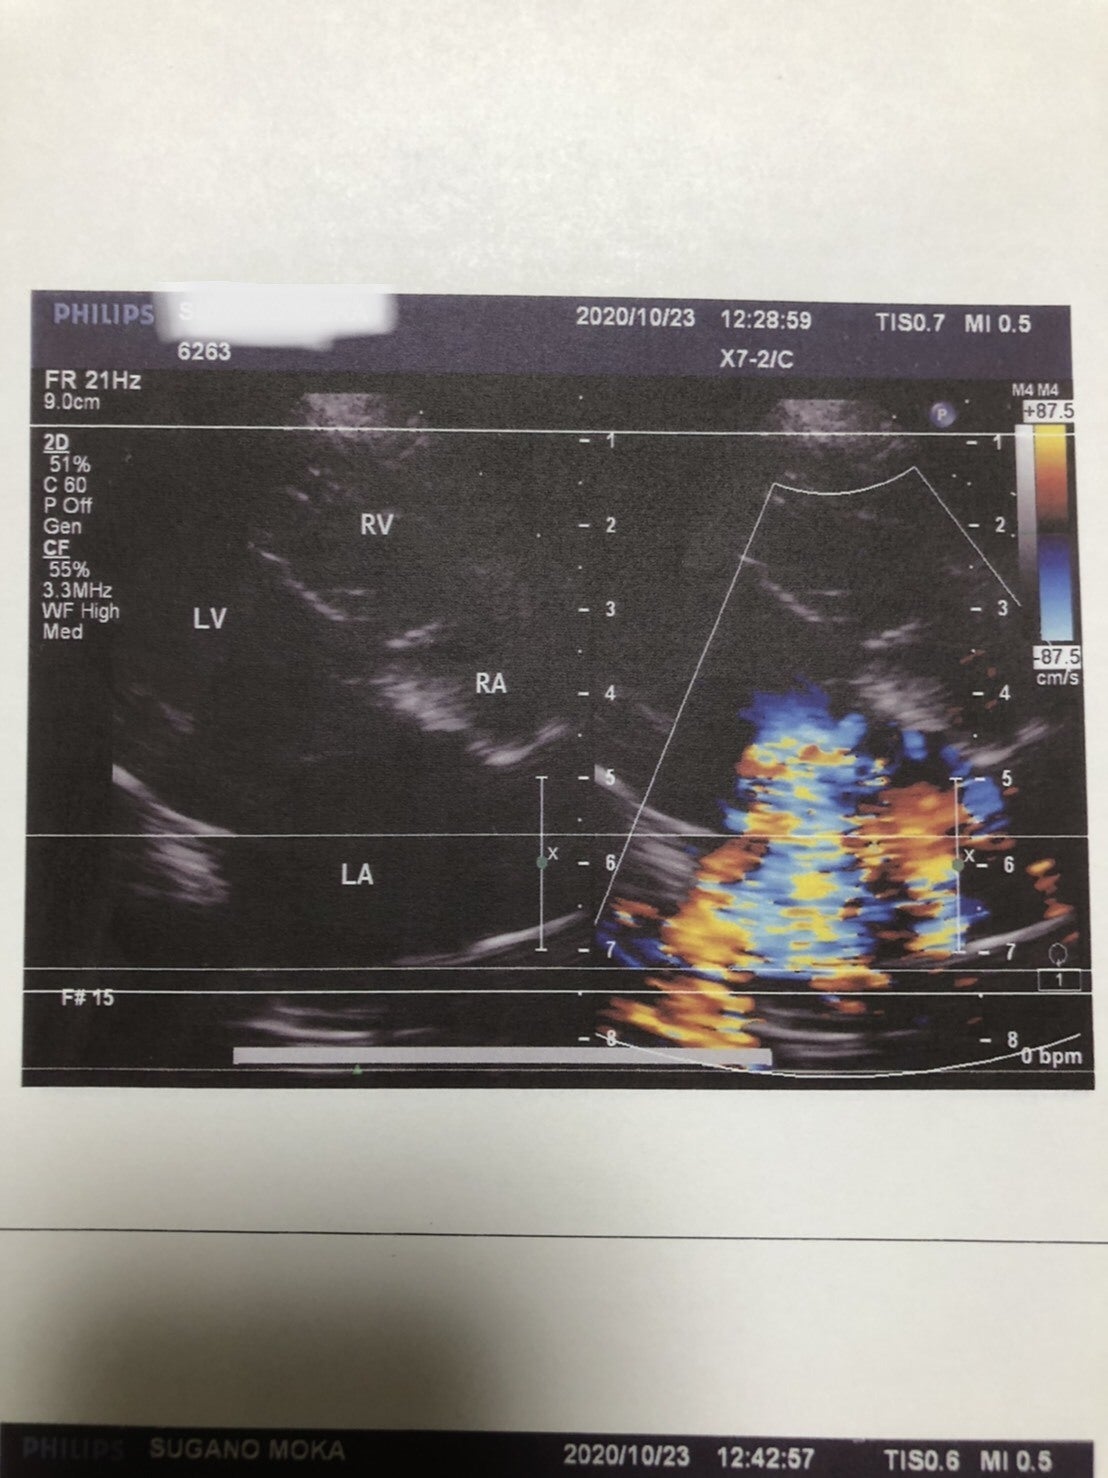

重度の収縮期逆流あり心エコーでは左房、左室ともに拡大が見られ、弁が完全に閉じず多量の逆流が認められる。この検査により強心剤の追加投与を勧められました→早めに紹介元のJ獣医さんのところで処方してもらう予定です。